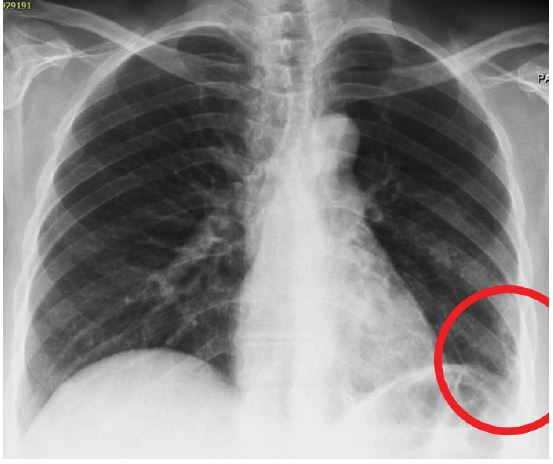

A 42-year-old male presented to our outpatient clinic with a 2-month history of persistent dry cough, mild exertional dyspnea, and occasional wheezing. He was a non-smoker with past history of Bronchial Asthma which was diagnosed 3 years back and patient was on Inhaled salbutamol on as needed basis. Clinical auscultation revealed a localized wheeze over the right lower lobe. Chest X-ray showed a suspicious opacity. CT chest revealed a well-defined lesion at the origin of the right lower lobe bronchus. Bronchoscopy visualized an endobronchial mass, and biopsy confirmed a typical carcinoid tumor.

Figure 2: CT axial image showing endobronchial lesion.